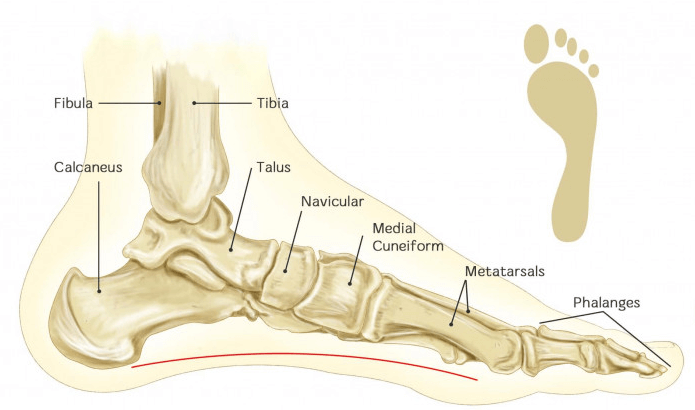

Platfod (Pes

Platfod (Pes

Platfod - Danske

Platfod - Danske

Effektiv behandling af platfod hulfod | KAISERSPORT.dk

Effektiv behandling af platfod hulfod | KAISERSPORT.dk

Hvad platfod? | Indlægsspecialisten

Hvad platfod? | Indlægsspecialisten

Diagnostik, evaluering og behandling platfødder børn | Ugeskriftet.dk

Diagnostik, evaluering og behandling platfødder børn | Ugeskriftet.dk

Diagnostik, evaluering og behandling platfødder børn | Ugeskriftet.dk

Diagnostik, evaluering og behandling platfødder børn | Ugeskriftet.dk

Platfod indlæg - Hvad er platfod? - Alt hvad skal vide!

Platfod indlæg - Hvad er platfod? - Alt hvad skal vide!